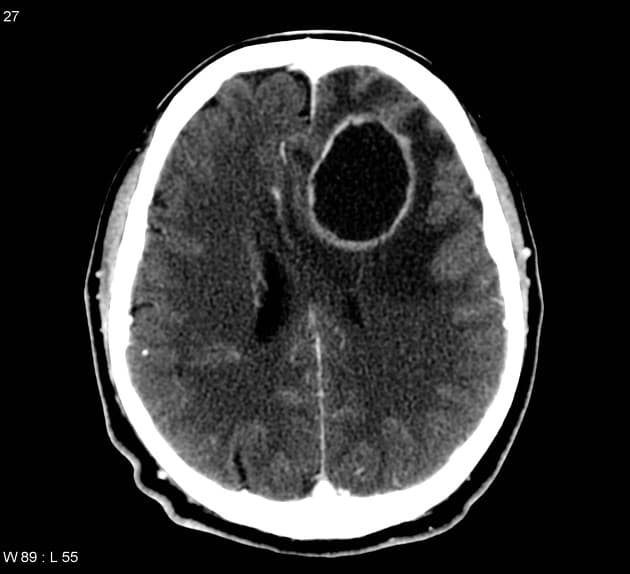

- Khối bắt thuốc dạng viền (ring-enhancing mass) ở thuỳ trán sau bên trái, kèm theo một lượng nhỏ phù vận mạch (vasogenic edema) xung quanh.

Lesion "hoàn hảo" bắt thuốc dạng viền, nhưng không phải là áp xe não (do không có hạn chế khuếch tán ở trung tâm trên hình ảnh khuếch tán – DWI và lượng phù tương đối ít). MAGIC DR là từ viết tắt gợi nhớ hữu ích cho hình ảnh này.